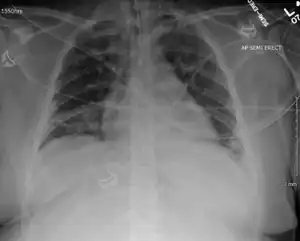

Enterovirus D68-associated acute respiratory distress syndrome in adult[17]